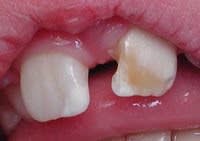

Le patient ci-dessous m'est adressé car ayant un "problème d'émail". Diagnostic ?

Biberon à la grenadine ??

J'aurais aussi pensé à "la carie du biberon"

caries du biberon

les inc inf definitives st "encore" saines mais ça ne va pas durer :sois convaincant ds ta motivation:)